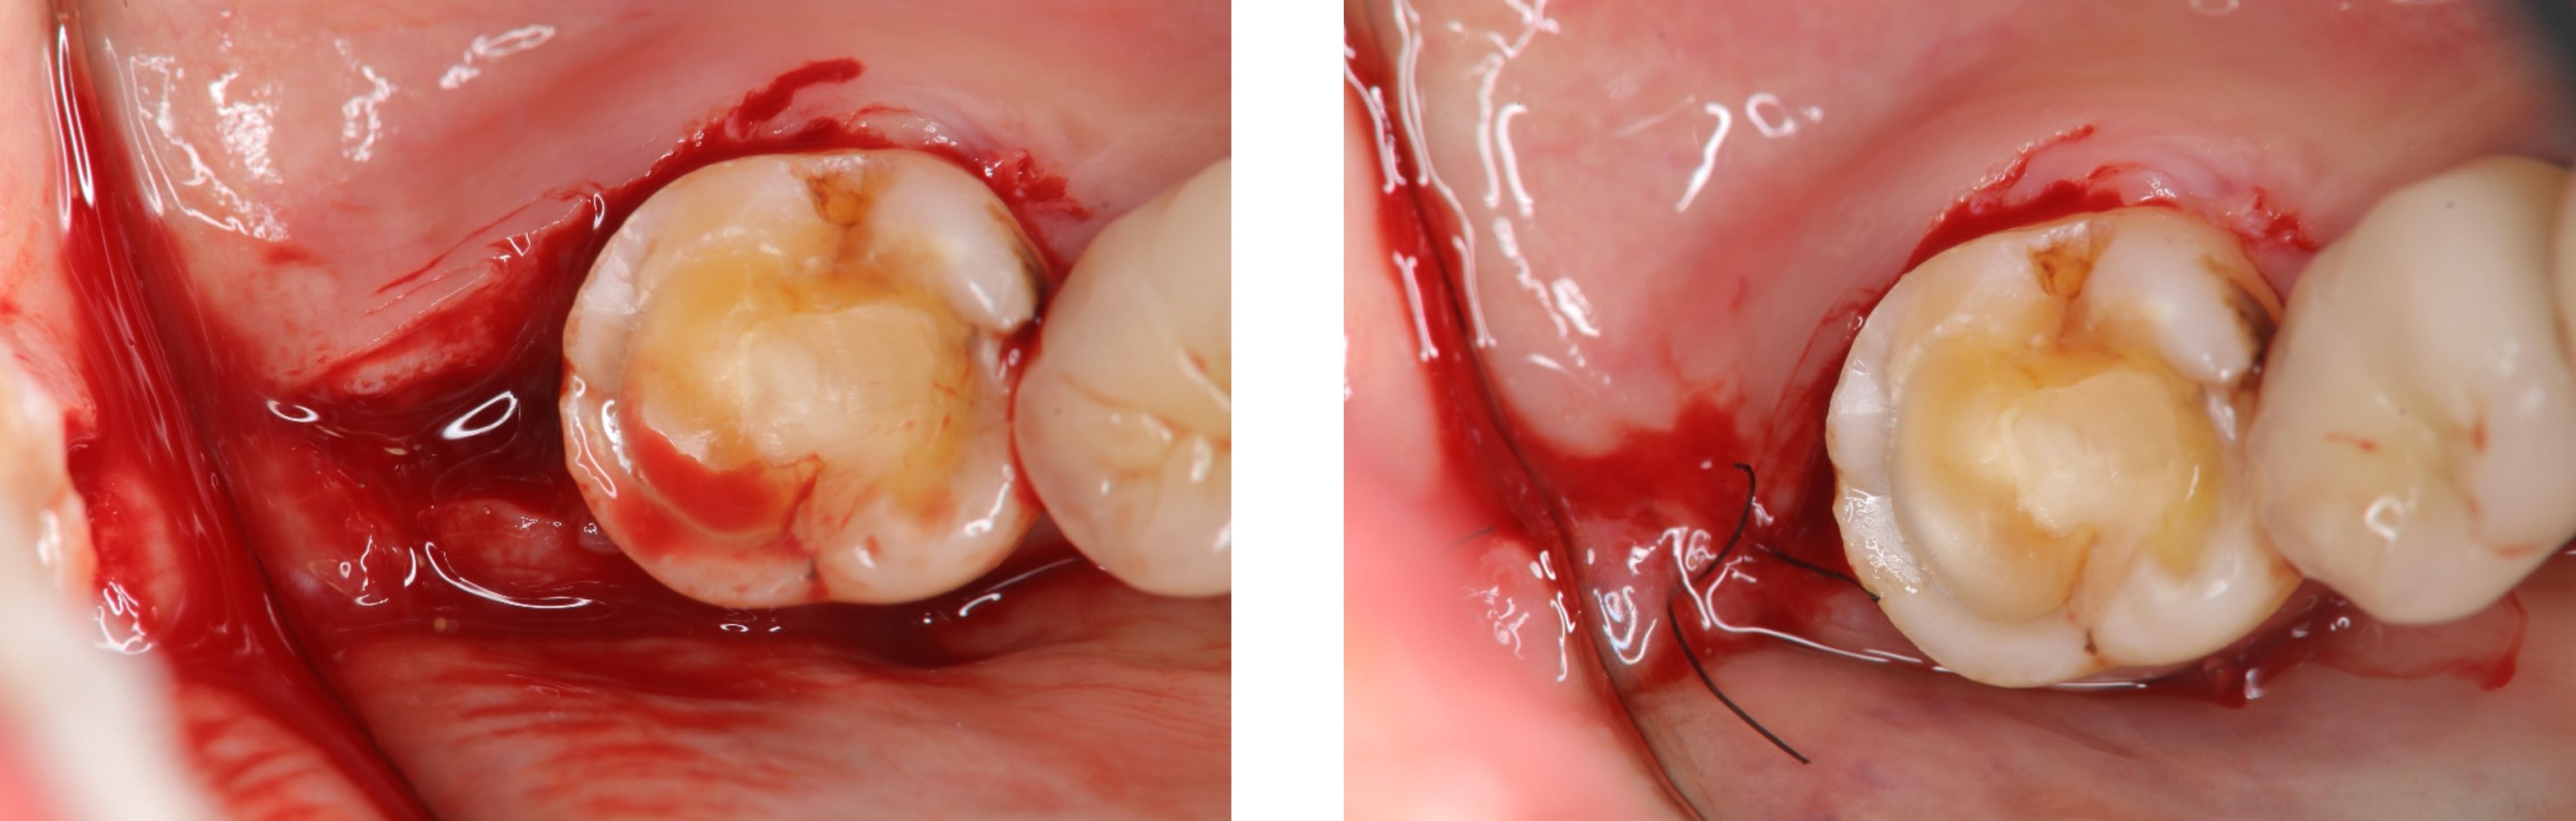

左下顎牙冠增長手術